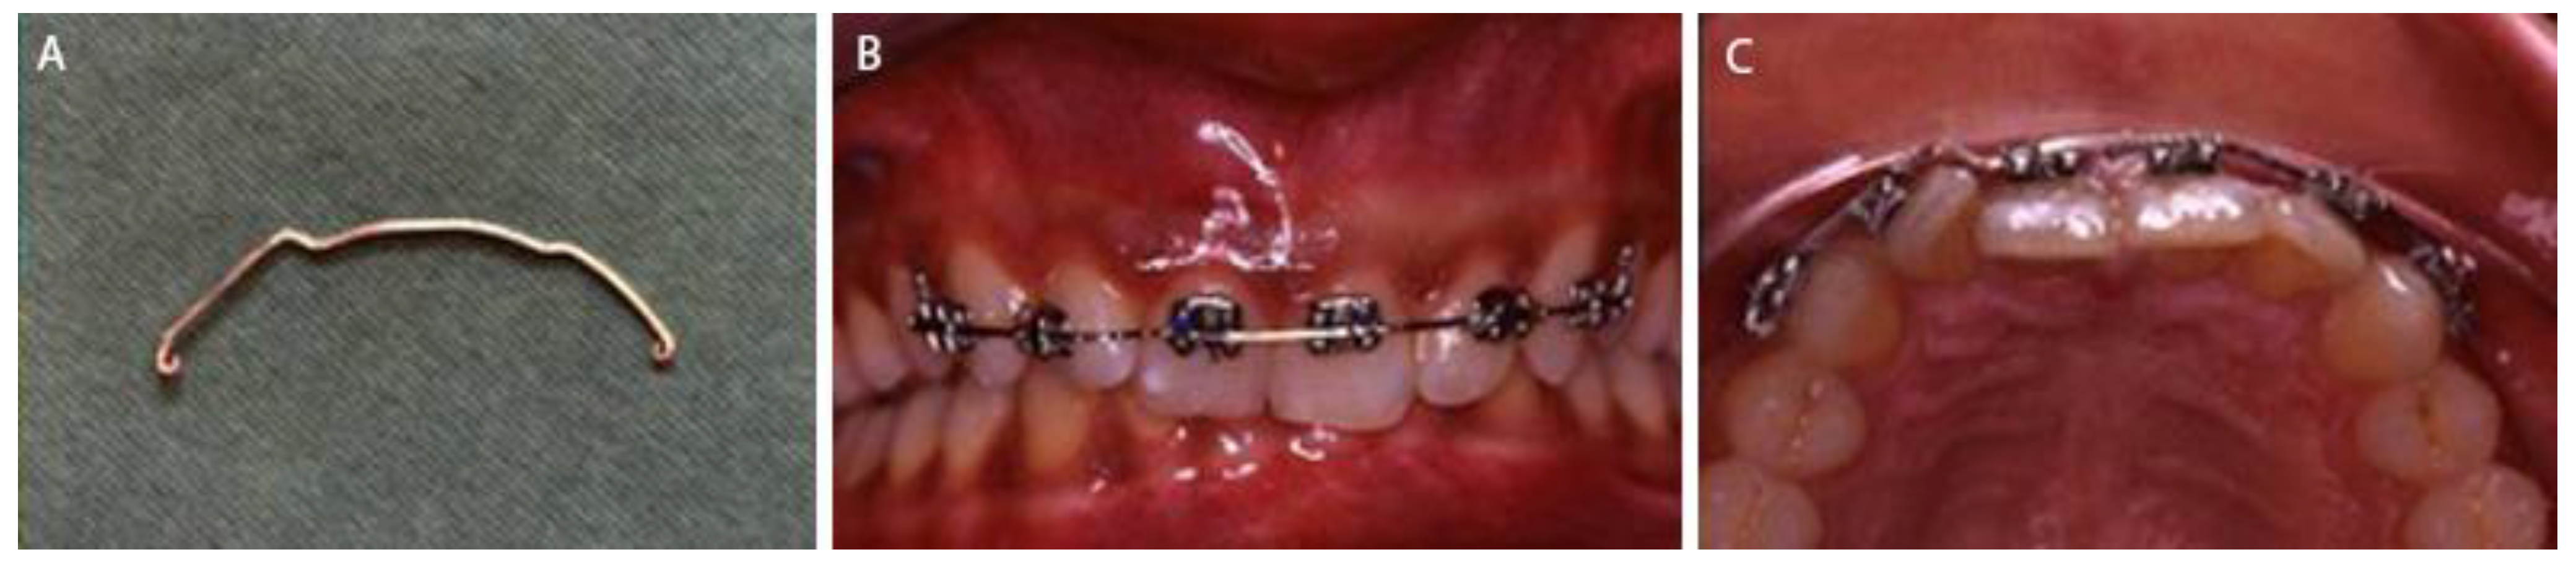

2. Case Presentation